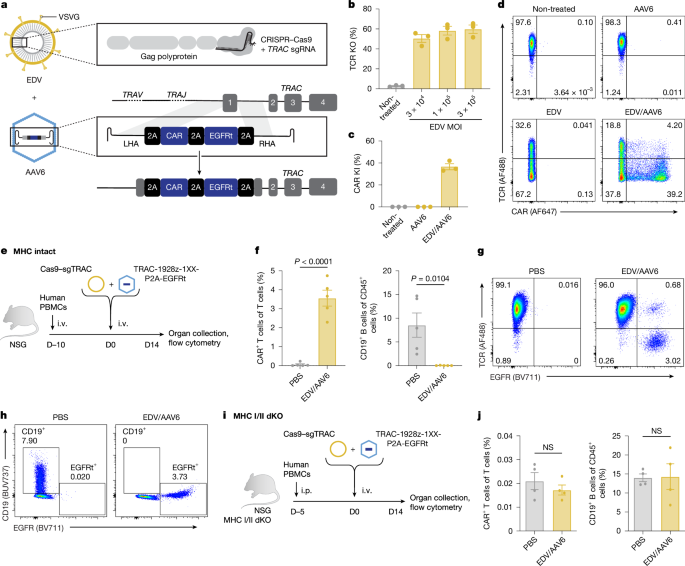

CRISPR makes enhanced cancer-fighting immune cells inside mice

Nature, Published online: 18 March 2026; doi:10.1038/d41586-026-00857-6Gene-editing technique promises a potentially safer way to create CAR T cells with a s...

A gene-editing method generates immunotherapeutic CAR T cells in the body

Nature, Published online: 18 March 2026; doi:10.1038/d41586-026-00634-5Laboratory-engineered immune cells called CAR T cells provide effective treatment for ...

In vivo site-specific engineering to reprogram T cells - Nature

Nature, Published online: 18 March 2026; doi:10.1038/s41586-026-10235-xStable and cell-specific transgene expression can be achieved through in vivo site-spe...